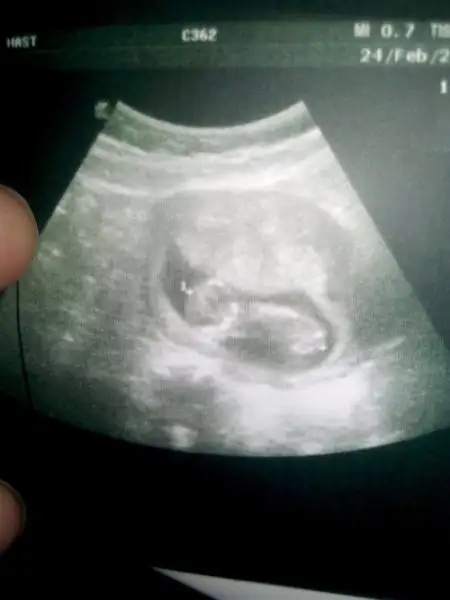

1456324577679-37548056.webp arkadaşlar yorumlar misiniz erkek mi kiz m​

Usg karındansa kız gibi,vajinalsa erkek gibi cnm

Karından usg.Canım ilk sayfada sağda durarsa kız yazıyordu sanki ama teşekkür ederim

Senin bebek sola yakin,vajinal usg ile karından usg farklı.o yüzden seninki karındanmis bu teoriye erkek oluyor cnm.